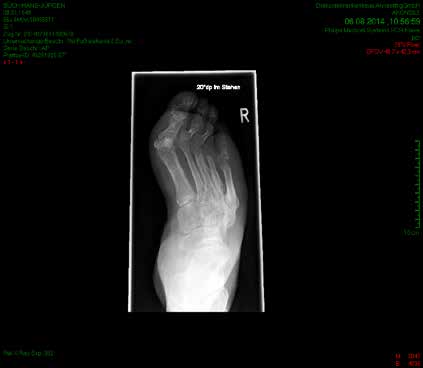

So erhielt ein 67-jähriger männlicher Patient nach operativer Versorgung mittels Fixateur externe neben einer Entlastung nur eine di_CAP-Therapie. Als Hauptdiagnose wurde eine sekundäre Fußfehlstellung in Pes-cavovarus-Position mit chronischem Ulcus am rechten Fußrand bei diabetischer Neuroosteoarthropathie festgehalten (Abb. 2); relevante Nebendiagnosen waren eine pAVK und diabetische Nephropathie. Als operative Therapie wurde eine Stellungskorrektur mit dem Hoffmannschen Fixateur externe durchgeführt (Abb. 3). Intraoperativ konnte eine bakterielle Besiedlung mit Escherichia coli, Enterococcus faecalis und Enterobacter cloacae nachgewiesen werden. Während des stationären Aufenthaltes wurde der Patient zweimal wöchentlich mit di_CAP behandelt. Nach seiner Entlassung erfolgte die Einbestellung zur di_CAP-Therapie nach der 4., 6. und 10. postoperativen Woche. Dabei wurde vor jeder Wundbehandlung ein Abstrich für eine mikrobiologische Untersuchung genommen. Im Verlauf kam es zu einer guten Wundheilung des anfänglich 3 × 5 cm messenden plantaren Ulcus, und in der 10. postoperativen Woche ließ sich eine fast vollkommene Wundheilung beobachten (Abb. 4). Ab der 1. postoperativen Woche war in den mikrobiologischen Abstrichen nur noch E. faecalis nachweisbar, und ab der 4. Woche konnte im Ulcus kein Keim mehr nachgewiesen werden. Aufgrund der geringen Patientenanzahl und der unregelmäßigen Wiedervorstellungen der Patienten konnte die Kohorte nicht suffizient im Verlauf beobachtet werden, um genügend Daten für eine prospektive Studie zu generieren. Die klinischen Erfahrungen der Verfasser decken sich jedoch mit Ergebnissen bisheriger Arbeiten zur di_CAP-Therapie.